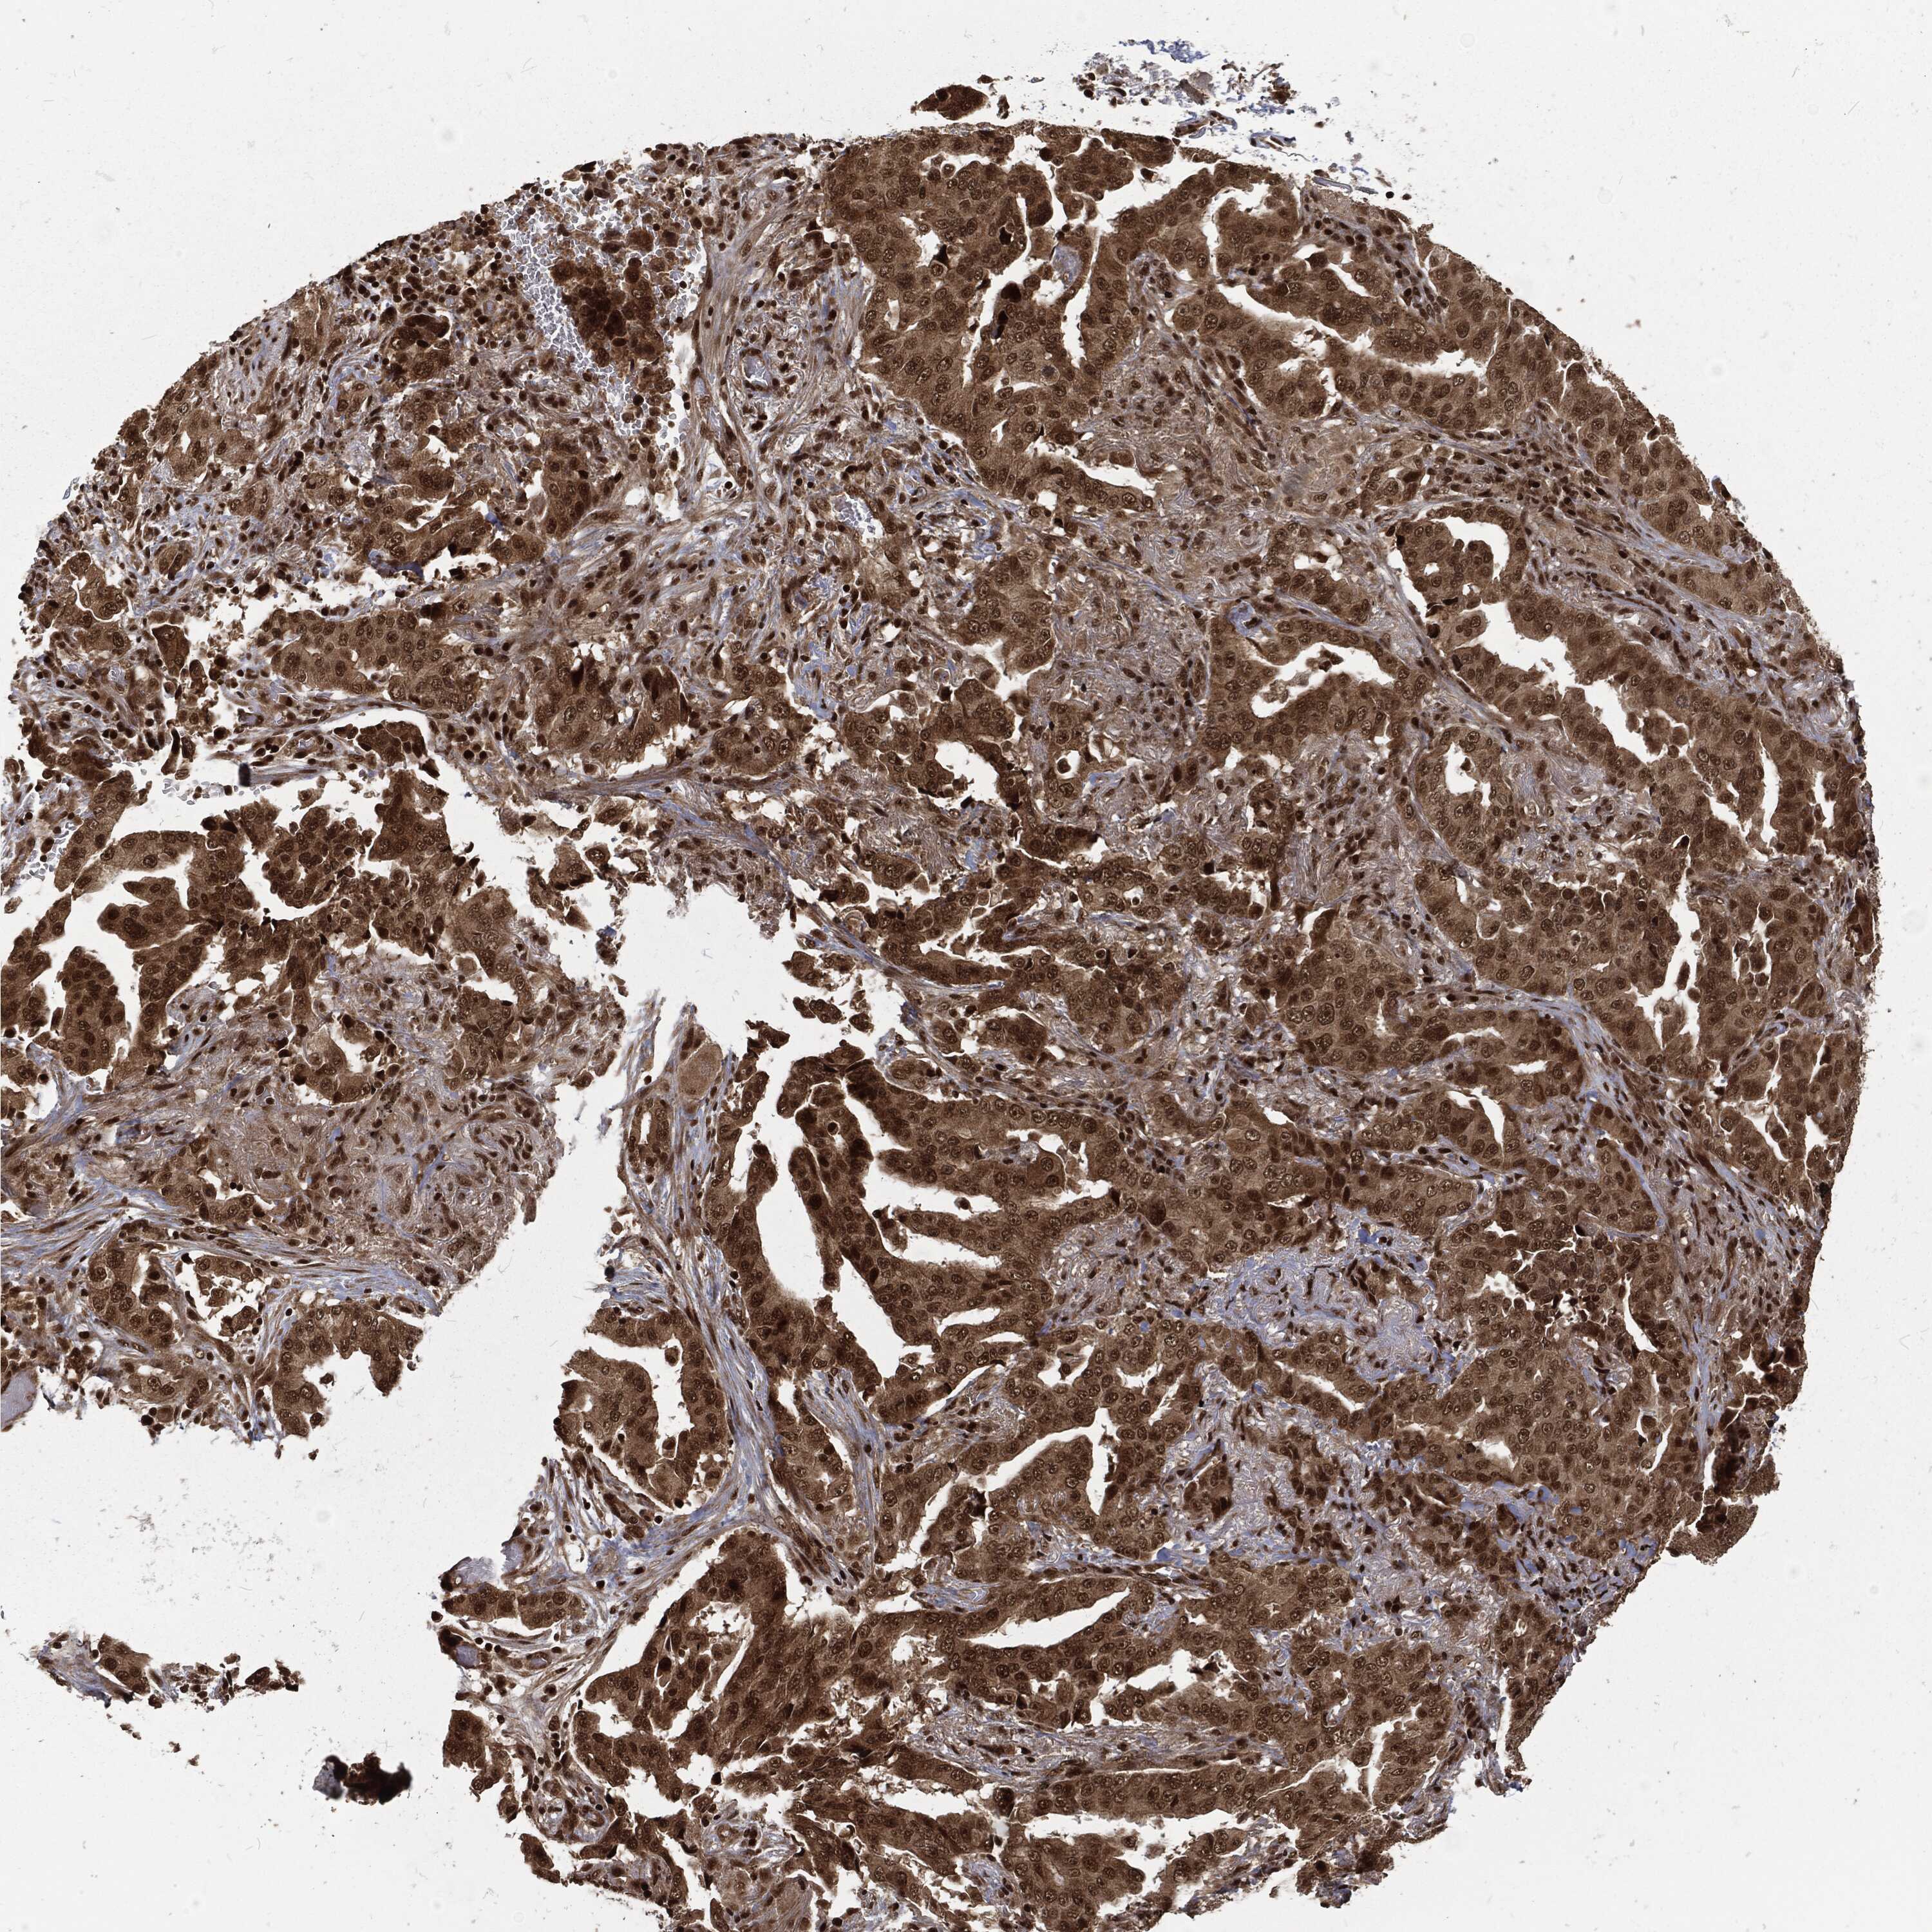

CANCER LUNG CANCER Show tissue menu

LUAD TCGA LUAD VALIDATION LUSC TCGA LUSC VALIDATION PROTEIN LUAD CPTAC PROTEIN LUSC CPTAC PROTEIN EXPRESSION